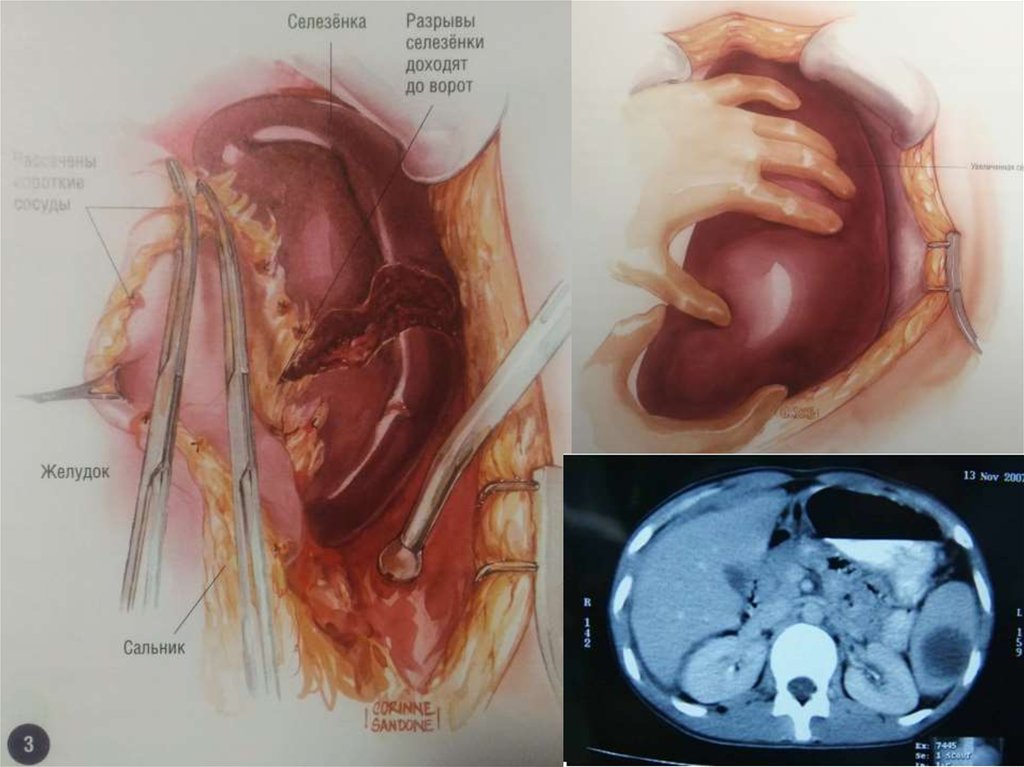

14. 1. Короткие желудочные артерии 2. Левая желудочно-сальниковая

2

1

1. Короткие

желудочные

артерии

2. Левая

желудочносальниковая